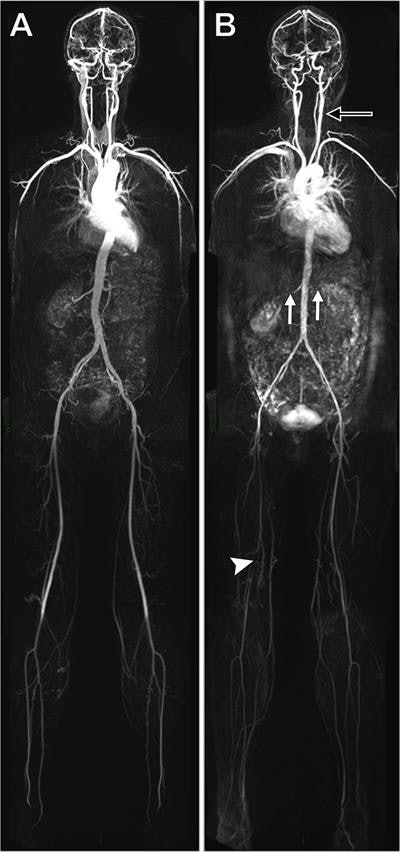

Whole-body MRA shows no evidence of disease in a 45-year-old woman (A). MRA in a 53-year-old woman (B) discovered extensive disease, including left carotid bulb stenosis (black arrow), bilateral renal artery stenosis (white arrows), and an occluded right superficial femoral artery (arrowhead). Image courtesy of RSNA and Radiology."This approach could stratify individuals for the presence of disease burden, which could inform further preventative therapy in the future," he said in a statement.

Houston and colleagues used whole-body MRA to assess 31 arterial segments in 1,513 people who were asymptomatic for atherosclerosis. The subjects had an average age of 53.5 years and were considered to have less than 20% risk of developing cardiovascular disease within 10 years (Radiology, May 1, 2018).

Using whole-body MRA, the researchers detected early atherosclerotic disease throughout the subjects' bodies and interpreted 99.4% of the potentially analyzable arterial segments. They found that almost half of the participants had at least one narrowed vessel and more than 25% had more than one narrowed vessel.